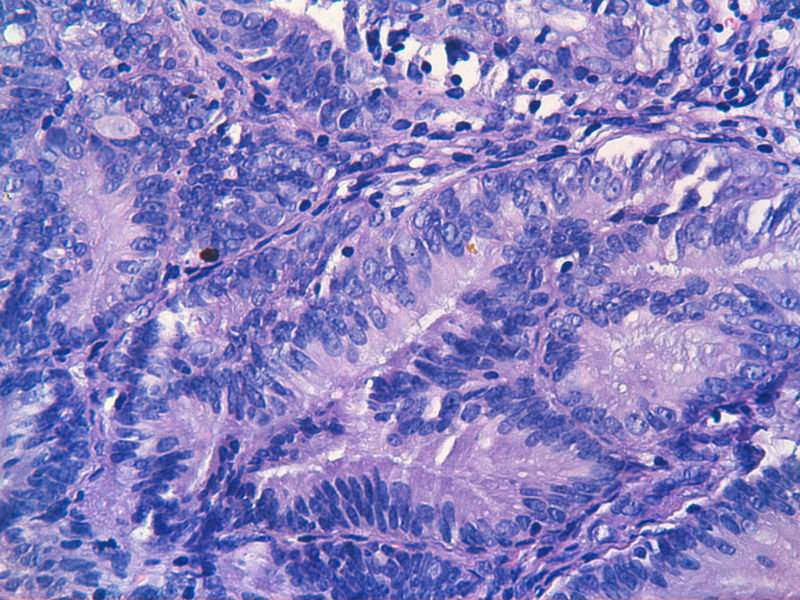

子宫内膜EIN?

子宫内膜EIN?图1

名称:图1

描述:image_2000y01m01d_08h08m34s

图13是做为正常对照的,图7、8、9、12显示的核大小不一,空泡状,形状不规则。女,48岁,宫血半年